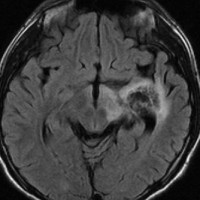

ICE化学療法投与開始から数日で小さくなります

この例は古いので第3脳室開窓術 ETV をしていません。左はICE化学療法前。中央は9日後。右は25日後です。閉塞性水頭症があっても1週間くらいで中脳水道が通って水頭症は改善します。ジャーミノーマであれば,ICE化学療法1コースでかなり縮小するはずです。このような顕著な効果がない時には,逆にジャーミノーマ以外の胚細胞腫瘍が混在していると考えた方がいいでしょう。多くは奇形腫の混在です。